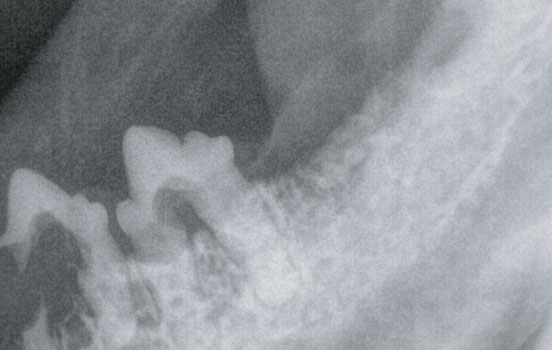

고양이 치아 흡수성 병변 (FORL)

고양이가조고양이의 구강 질환 중 가장 일반적이며 통증이 심한 질환입니다.

치아의 에나멜질과 심부의 상아질에 미란이 일어납니다.

육안적으로 확인되는 경우도 있으나, 정확한 평가를 위해서는 치과 방사선을 촬영해 봐야합니다.

병변이 관찰될 경우, 영향을 받은 치아 뿐만 아니라 전체 치아를 발치해야 하기 때문에

정확한 진단과 치료가 필요합니다.